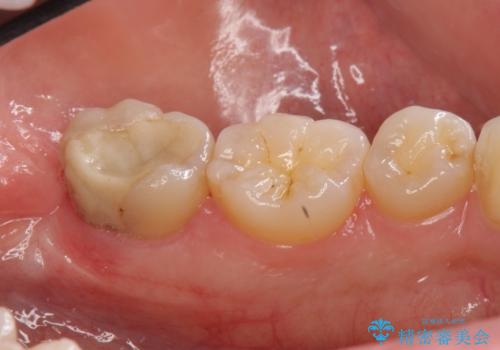

他院でつめていたものは、セメントで、一時的な詰め物がなされていました。(中は虫歯になっていました。)

虫歯を取ると、歯ぐきの奥深くまで虫歯になっており、そのままではきちんと修復することが難しい状態でした。